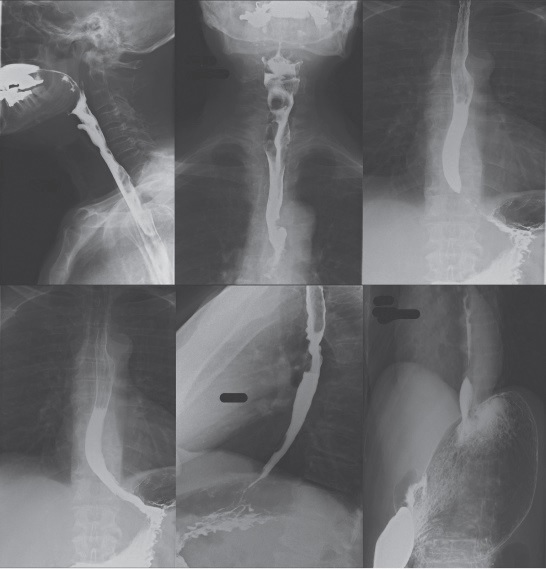

What is a fluoroscopy, or barium swallow?

This is an x-ray examination that looks at your oesophagus, (the tube that leads to your stomach). We will ask you to drink a chalky white liquid called barium, which shows up on the x-rays. We take x-ray pictures as you swallow the barium.

When you arrive you will be taken to a cubicle and asked to change into a hospital gown. Please feel free to bring your own dressing gown if you wish. In the x-ray room you will be asked to stand in front of the x-ray camera and you will be given the barium drink. Pictures are taken as you drink the liquid. X-ray images may be taken at different angles to show the oesophagus and stomach.